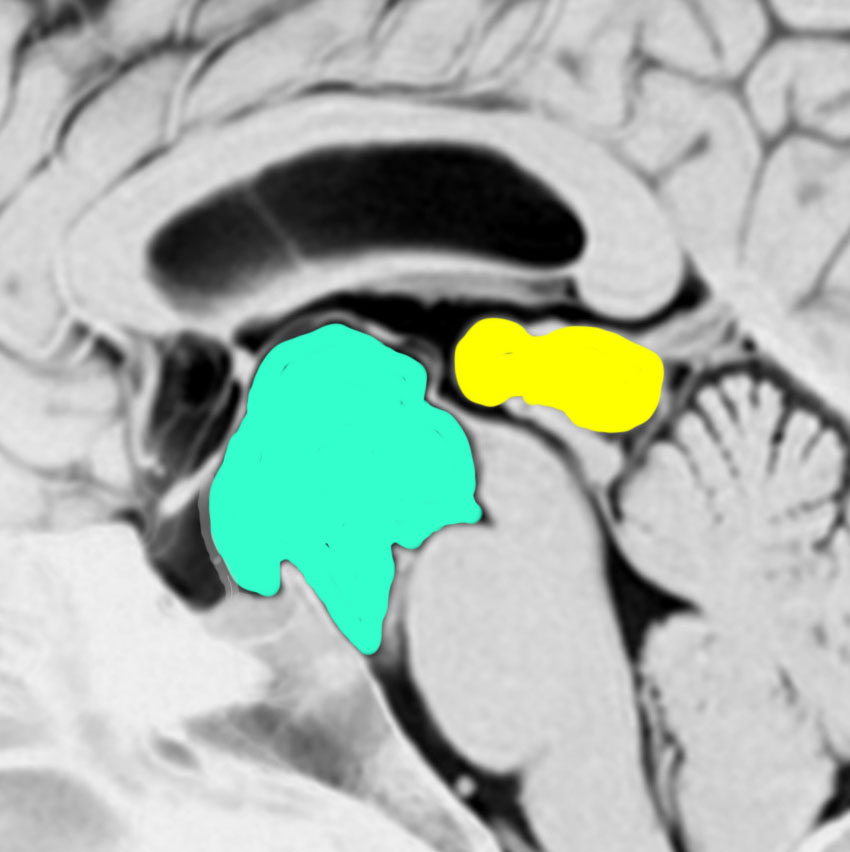

鞍上部クモ膜のう胞

20歳代の女性の無症候性のものです。水色に塗ったのがクモ膜のう胞です。特徴的なのは,下垂体柄が長〜く伸びて細くなっていることです,でも下垂体障害はでません。珍しいことですが,松果体のう胞(黄色の部分)が合併しています。治療の必要がないものです。